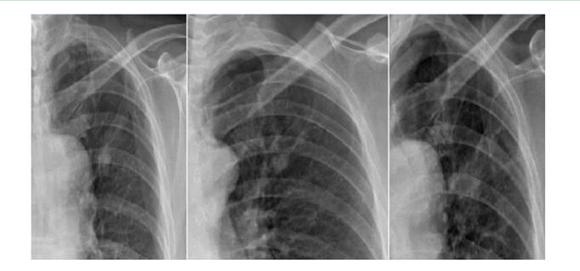

案例一:

第一年 第二年 第三年

案例解析:

在该案例中,病患在单一胸片检查中,诊断出左上肺高密度结节影,前两次在胸片摄影检查得出的诊断结果并无大碍。相隔一年再去复查被误诊为“结核硬结灶”,并针对此而治疗。但是,到了第三年之后,再次诊断发现结节影明显增大,后才被确诊为是肺癌,但为时已晚;如使用具备可视化点片功能的DR设备,胸片与胸透无缝结合,在透视下对“高密度结节影”全方位、多角度的高清点片获取更多的确诊信息,进一步病理分析,第一时间得出确诊结果,做到早发现、早治疗,结果将会截然不同。